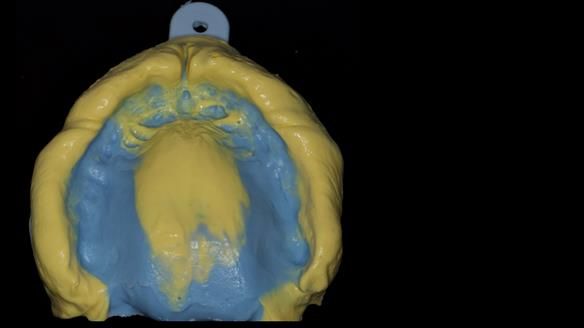

We provided her with an immediate upper denture (Mk 1), followed by a definitive metal-based upper denture (Mk 2). A lower removable partial denture was discussed, to be made only if needed once the upper treatment was complete. However, at review, this wasn’t necessary — Adnana had excellent neuromuscular control and function, even with a shortened dental arch (SDA).

Rowan, Sam Hesketh and Chris Hesketh provided the stunning technical work. I am very lucky to have them.